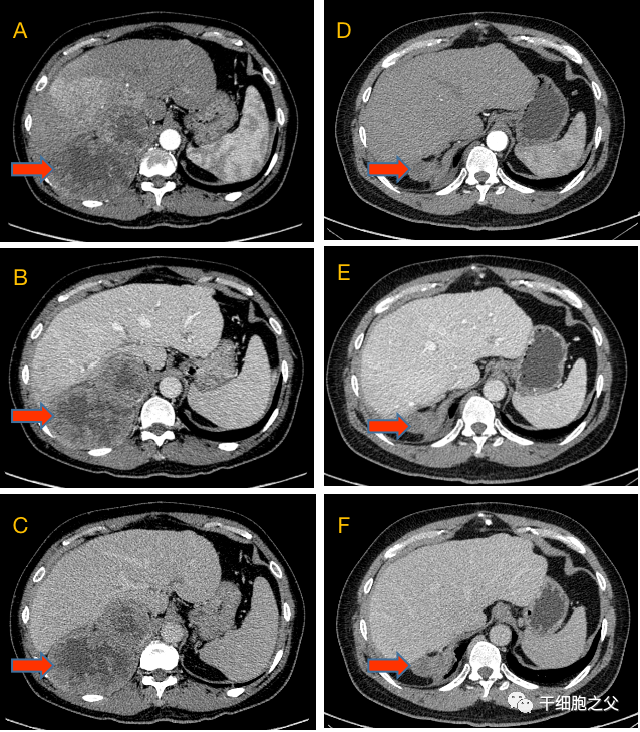

治疗前(A、B、C)和治疗54周后(D、E、F)上腹部增强CT对比